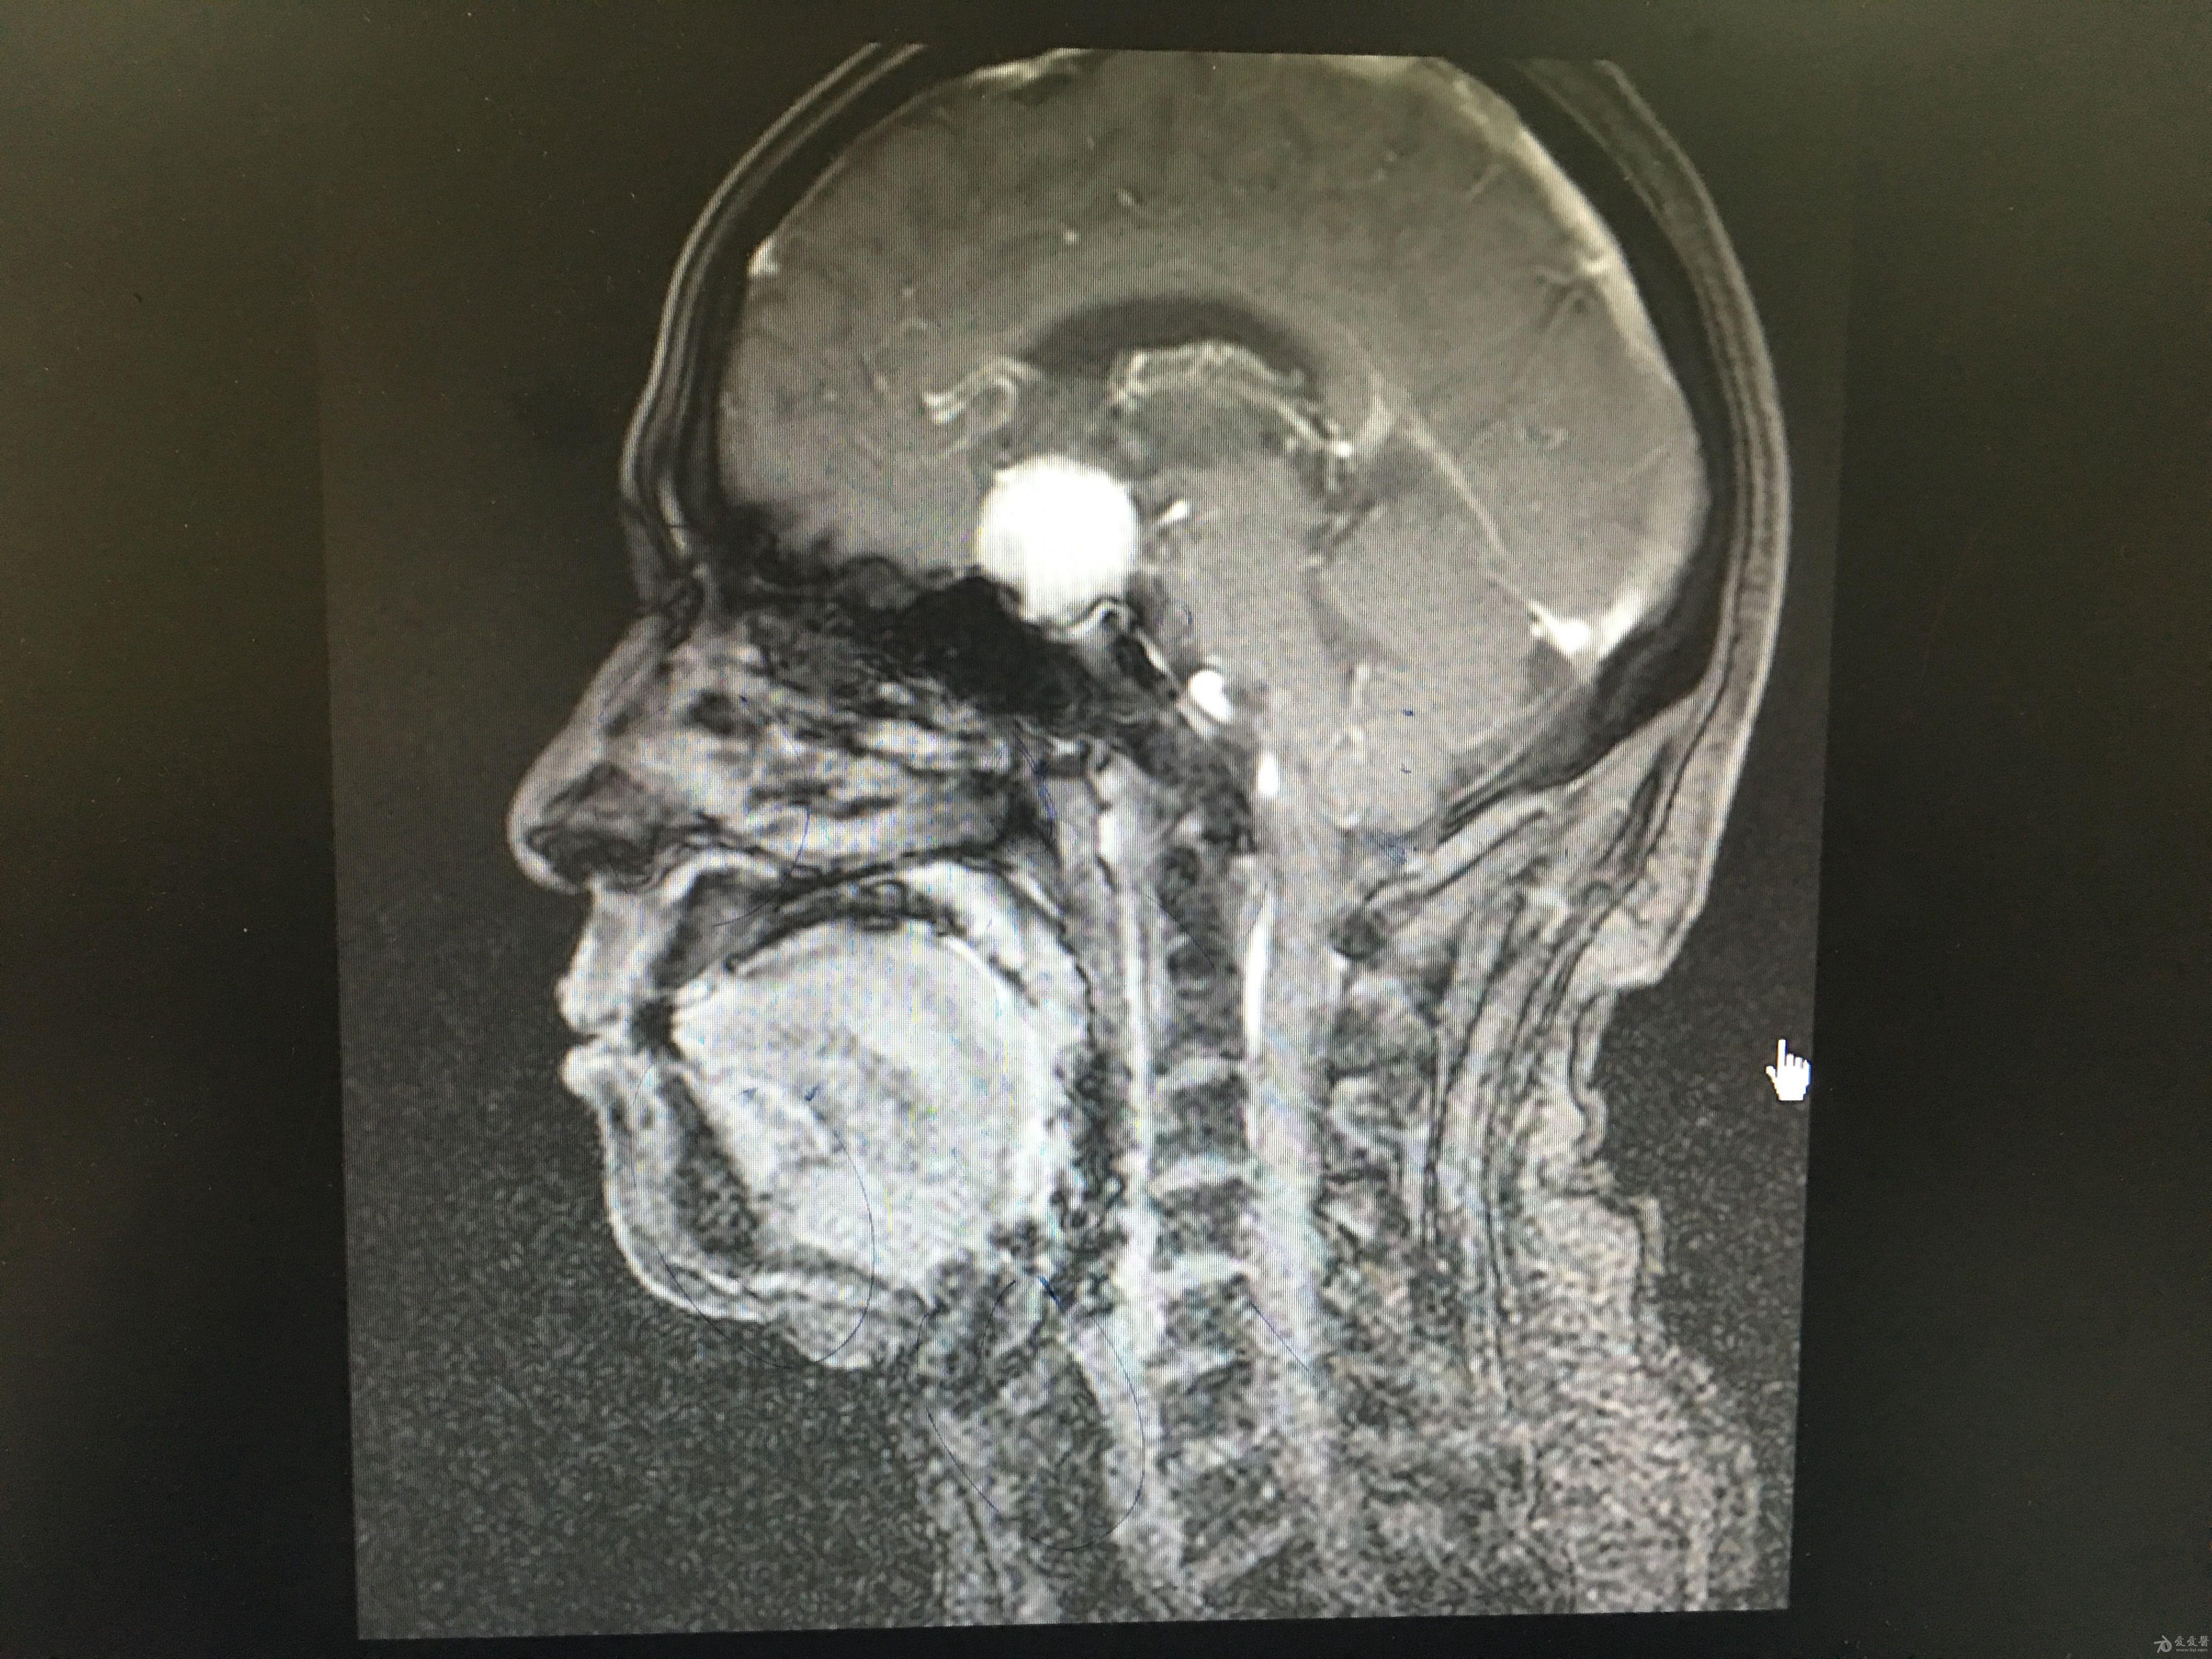

分享一例鞍区脑膜瘤手术病例原创

图片尺寸4032x3024